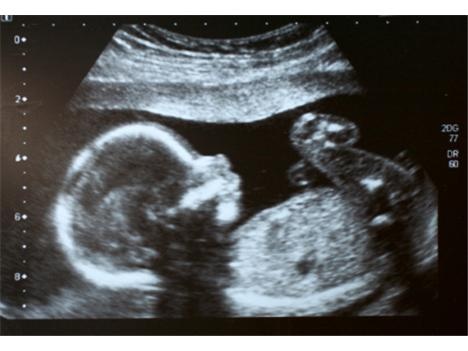

Cituji Gandalf: Každá těhotná prochází screeningem na Downův syndrom v 16. týdnu těhotenství.

To ano, ale ten ve 12.tt je přesnější. Tady ten v tom 16.tt to už tak neodhadne.

Mě ho dělali ve 12 týdnu, jenže toto vyšetření není ani zdaleka dostačující.

Můj gynekolog mi řekl, že se mýlí až v 50%, a z toho se opravdu nedá téměř nic usoudit.